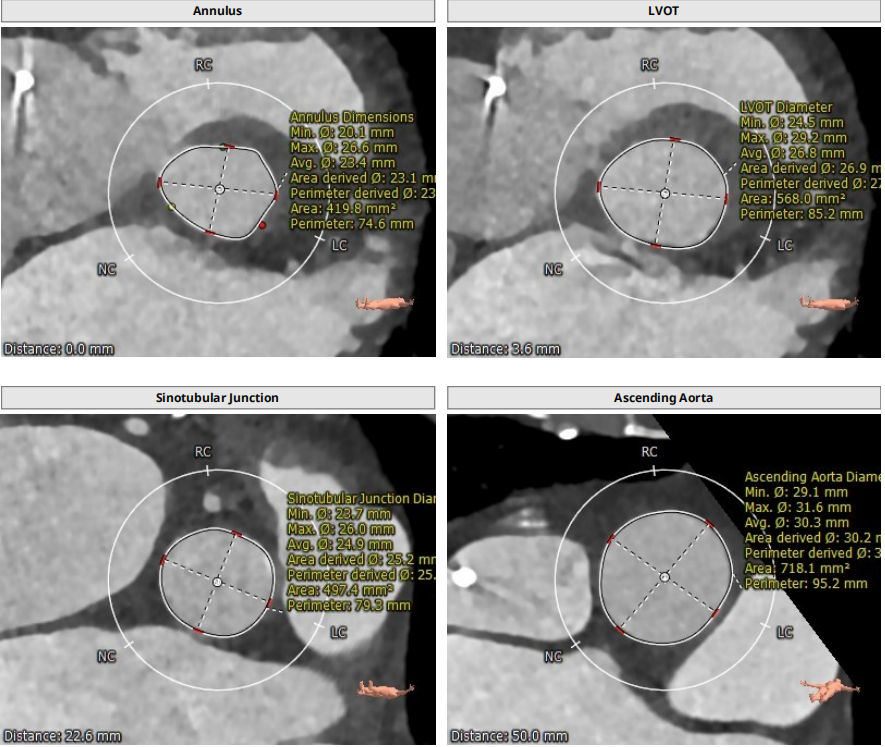

三叶瓣轻度钙化,右无可见钙化脊,瓣叶可见增厚,右冠高度可,左冠开口层面可见瓣叶,升主动脉未见明显扩张,法式窦及窦管交界稍小,两侧股动脉入路可,二尖瓣机械瓣置换术后。瓣环平均径23.7mm,LVOT26.8mm,STJ24.9mm,RCA18.4mm,LCA11.4mm。

2. STJ结构偏小且整体窦部结构不大,左冠瓣叶高度可达冠脉口,术中球囊预扩无造影剂下判断冠脉灌注情况难度大;